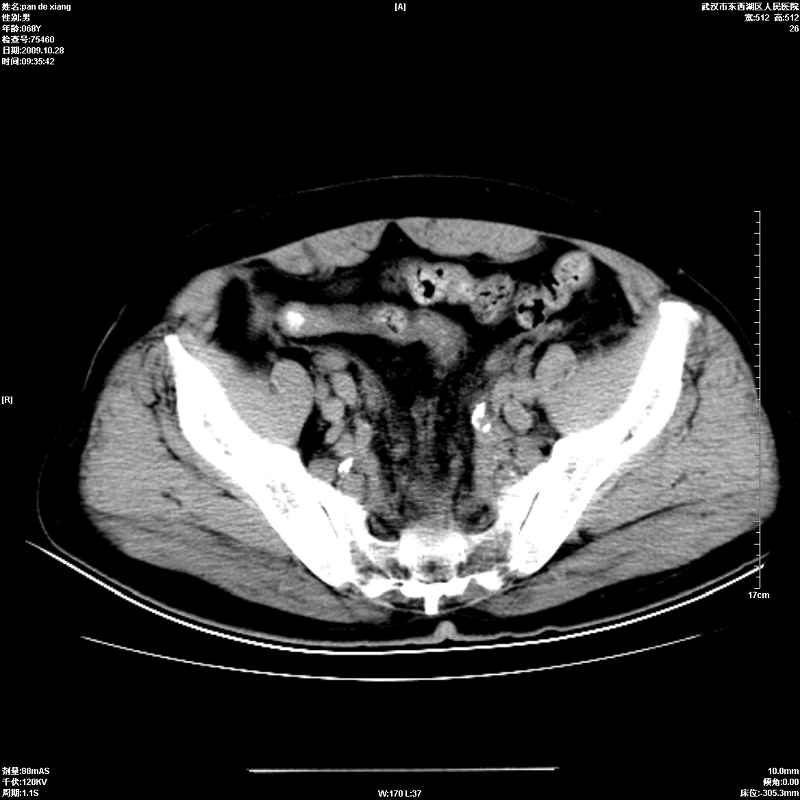

以下是引用杀毒软件在2009-10-28 20:41:00的发言:[br]结合临床考虑---白血病双肾改变或淋巴瘤。

以下是引用zxl51642在2009-10-29 9:59:00的发言:[br]结合临床“单克隆免疫球蛋白血症”,考虑双肾为继发损害并肾功能不全(尿中大量igg及少量iga、igm等大分子免疫球蛋白滤出所致继发损害),椎前软组织肿块为髓外造血。与浆细胞瘤有区别,平扫时有战友说的很清楚。